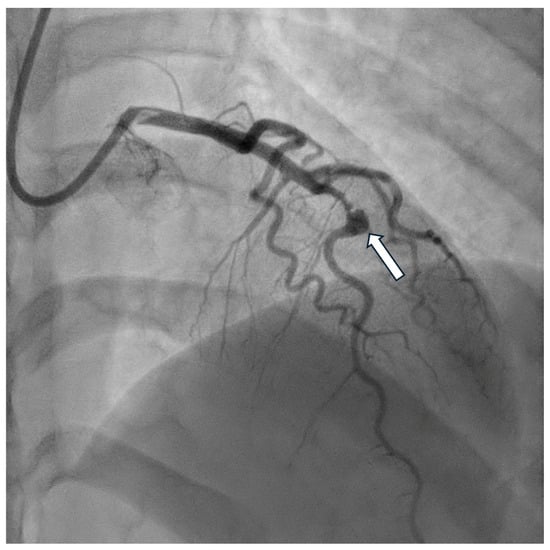

Owing to the significantly higher resolution of imaging, optical coherence tomography (OCT) allows for a detailed assessment of the coronary vessel, including the morphology of atherosclerotic plaques and aneurysm complications, i.e., the presence of a thrombus (Figure 5 and Figure 6). However, the limitation is the limited penetration depth. In the case of larger aneurysms, it is impossible to visualize the entire cross-section of the vessel [].

Figure 5. Coronary angiography of the fusiform aneurysm (arrow) of the left anterior descending artery.